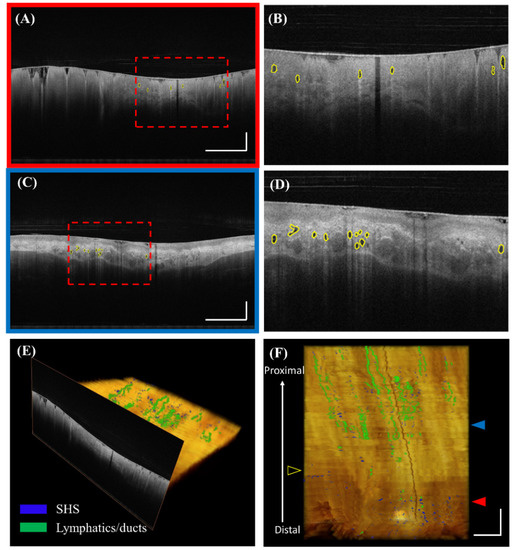

The automatically detected SHSs can be visualized in 2D and 3D. Figure 4 illustrates an example where the SHSs were segmented and labeled by the algorithm in both BE and squamous regions. In the 3D view, the SHSs (blue) appeared as local, spotted features, whereas the lymphatics and ducts (green) formed elongated, connected “pipes” that traversed many images longitudinally.

Figure 4. Visualization of automatically detected SHSs. (A) Volumetric laser endomicroscopy (VLE) image with automatically detected SHSs under the BE region in polar coordinates. (B) Corresponding zoomed-in view. (C) Automatically detected SHSs under the squamous region. (D) Corresponding zoomed-in view. (E) and (F) 3D visualization of SHSs (blue) and lymphatics/ducts (green). The registration line on the balloon is also visible as a dark band traversing the entire pullback. The red and blue solid arrows indicate the cross-sectional position of (A) and (C), respectively. The yellow hollow arrow indicates the maximum extent of BE. Scale bars: 1 mm.